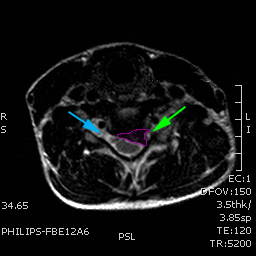

Ασθενής με αυχενοβραχιόνιο σύνδρομο, κήλη αυχενικού δίσκου με πίεση επί του νεύρου (πράσινο βέλος) |